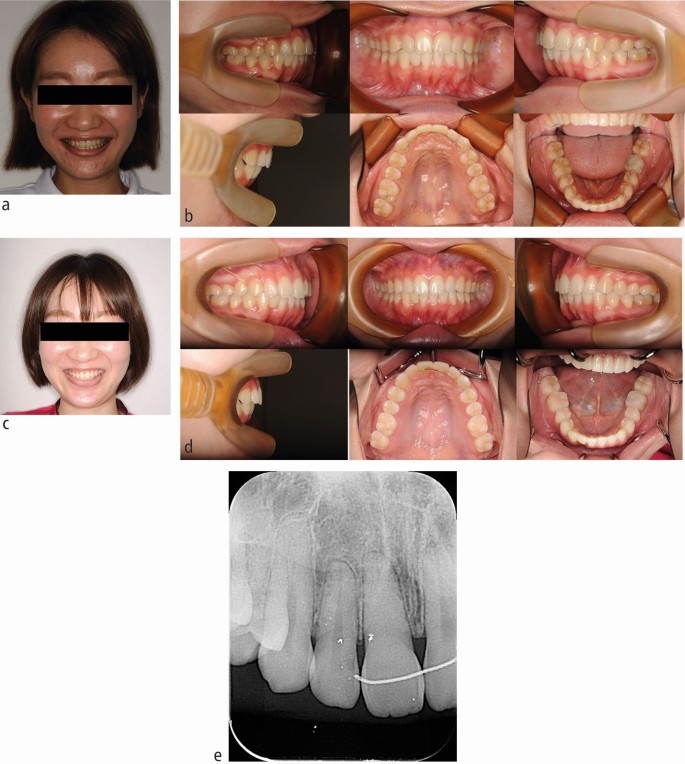

The patient was a 24-year-old woman with a chief complaint of a gummy smile. Although orthognathic surgery was previously recommended, the patient refused to undergo surgery. The pre-treatment smiling facial photograph revealed excessive gingival display (Fig. 1A). Intra-oral photographs revealed a Class I molar relationship, deep overbite, and congenitally missing mandibular right lateral incisor (Fig. 1B). A panoramic radiograph showed existence of all third molars except the maxillary right third molar (Fig. 1C). Accordingly, the patient was diagnosed with a severe deep bite with a gummy smile and missing mandibular right lateral incisor.

For orthodontic treatment, 0.018-inch standard edgewise brackets were bonded on the maxillary teeth. Two self-drilling TADs (diameter, 1.6 mm; length, 8 mm; Dual Top Auto Screw; Jeil Medical Corp, South Korea) were inserted into the buccal alveolar bone between the maxillary lateral incisors and canines to intrude the maxillary anterior teeth using an elastic chain. Before completion of opening the bite, positive crown torque of the upper incisors was achieved by torque moment generated with intruded force (Fig. 2A). After opening the bite, brackets were bonded on the mandibular teeth to create space between mandibular right central incisor and canine. However, after 12 months of intrusion, the crown of the maxillary right central incisor showed grey discoloration and a negative response to electric pulp tests (Fig. 2B). Furthermore, the patient reported severe spontaneous pain only in this tooth two days before visiting our clinic. However, no significant radiographic change was observed around the root apex of the maxillary right central incisor. Notably, moderate apical root resorption was observed in the maxillary right lateral incisor by the dental x-ray (Fig. 2C). From these symptoms, we thought traumatic pulp injury occurred on the right central incisor. Therefore, we removed the orthodontic force on the maxillary incisors with passive wire ligations between TADs and the upper canines, and 60 mg of loxoprofen sodium was administered three times a day for seven days. No more intrusion force to the upper incisors was applied because opening the bite had been completed. Six months after stopping orthodontic treatment, resolution of the crown discoloration was observed and the response to electric pulp testing was restored (Fig. 3A). Periapical radiography revealed a distinct radiolucency at the root apex (Fig. 3B). Two years after initiation of orthodontic treatment, the patient's gummy smile and overbite were corrected with a good intercuspal relationship. The missing mandibular right lateral incisor was replaced by direct bonding (Fig. 4A, Fig. 4B). Follow-up at four years after beginning of retention revealed stable smile aesthetics and tooth positions (Fig. 4C, Fig. 4D). Periapical radiographs showed marked root canal obliteration in the maxillary right central incisor and remodelling of the root apex in the maxillary right lateral incisor (Fig. 4E). The wire sequence used in this case is shown in Table 1.

(A) Intrusion of the maxillary anterior teeth using an elastic chain from temporary anchorage devices. (B) Intra-oral photograph 12 months after anterior teeth intrusion. The crown of the maxillary right central incisor showed discoloration. (C) Dental x-ray immediately after discoloration of the crown

(A) Post-treatment smiling facial photograph. (B) Post-treatment intra-oral photographs. (C) Smiling facial photograph four years after retention. (D) Intra-oral photographs four years after retention. (E) Dental x-ray at four years after retention. Marked root canal obliteration in the maxillary right central incisor and remodelling of the root apex in the maxillary right lateral incisor were shown